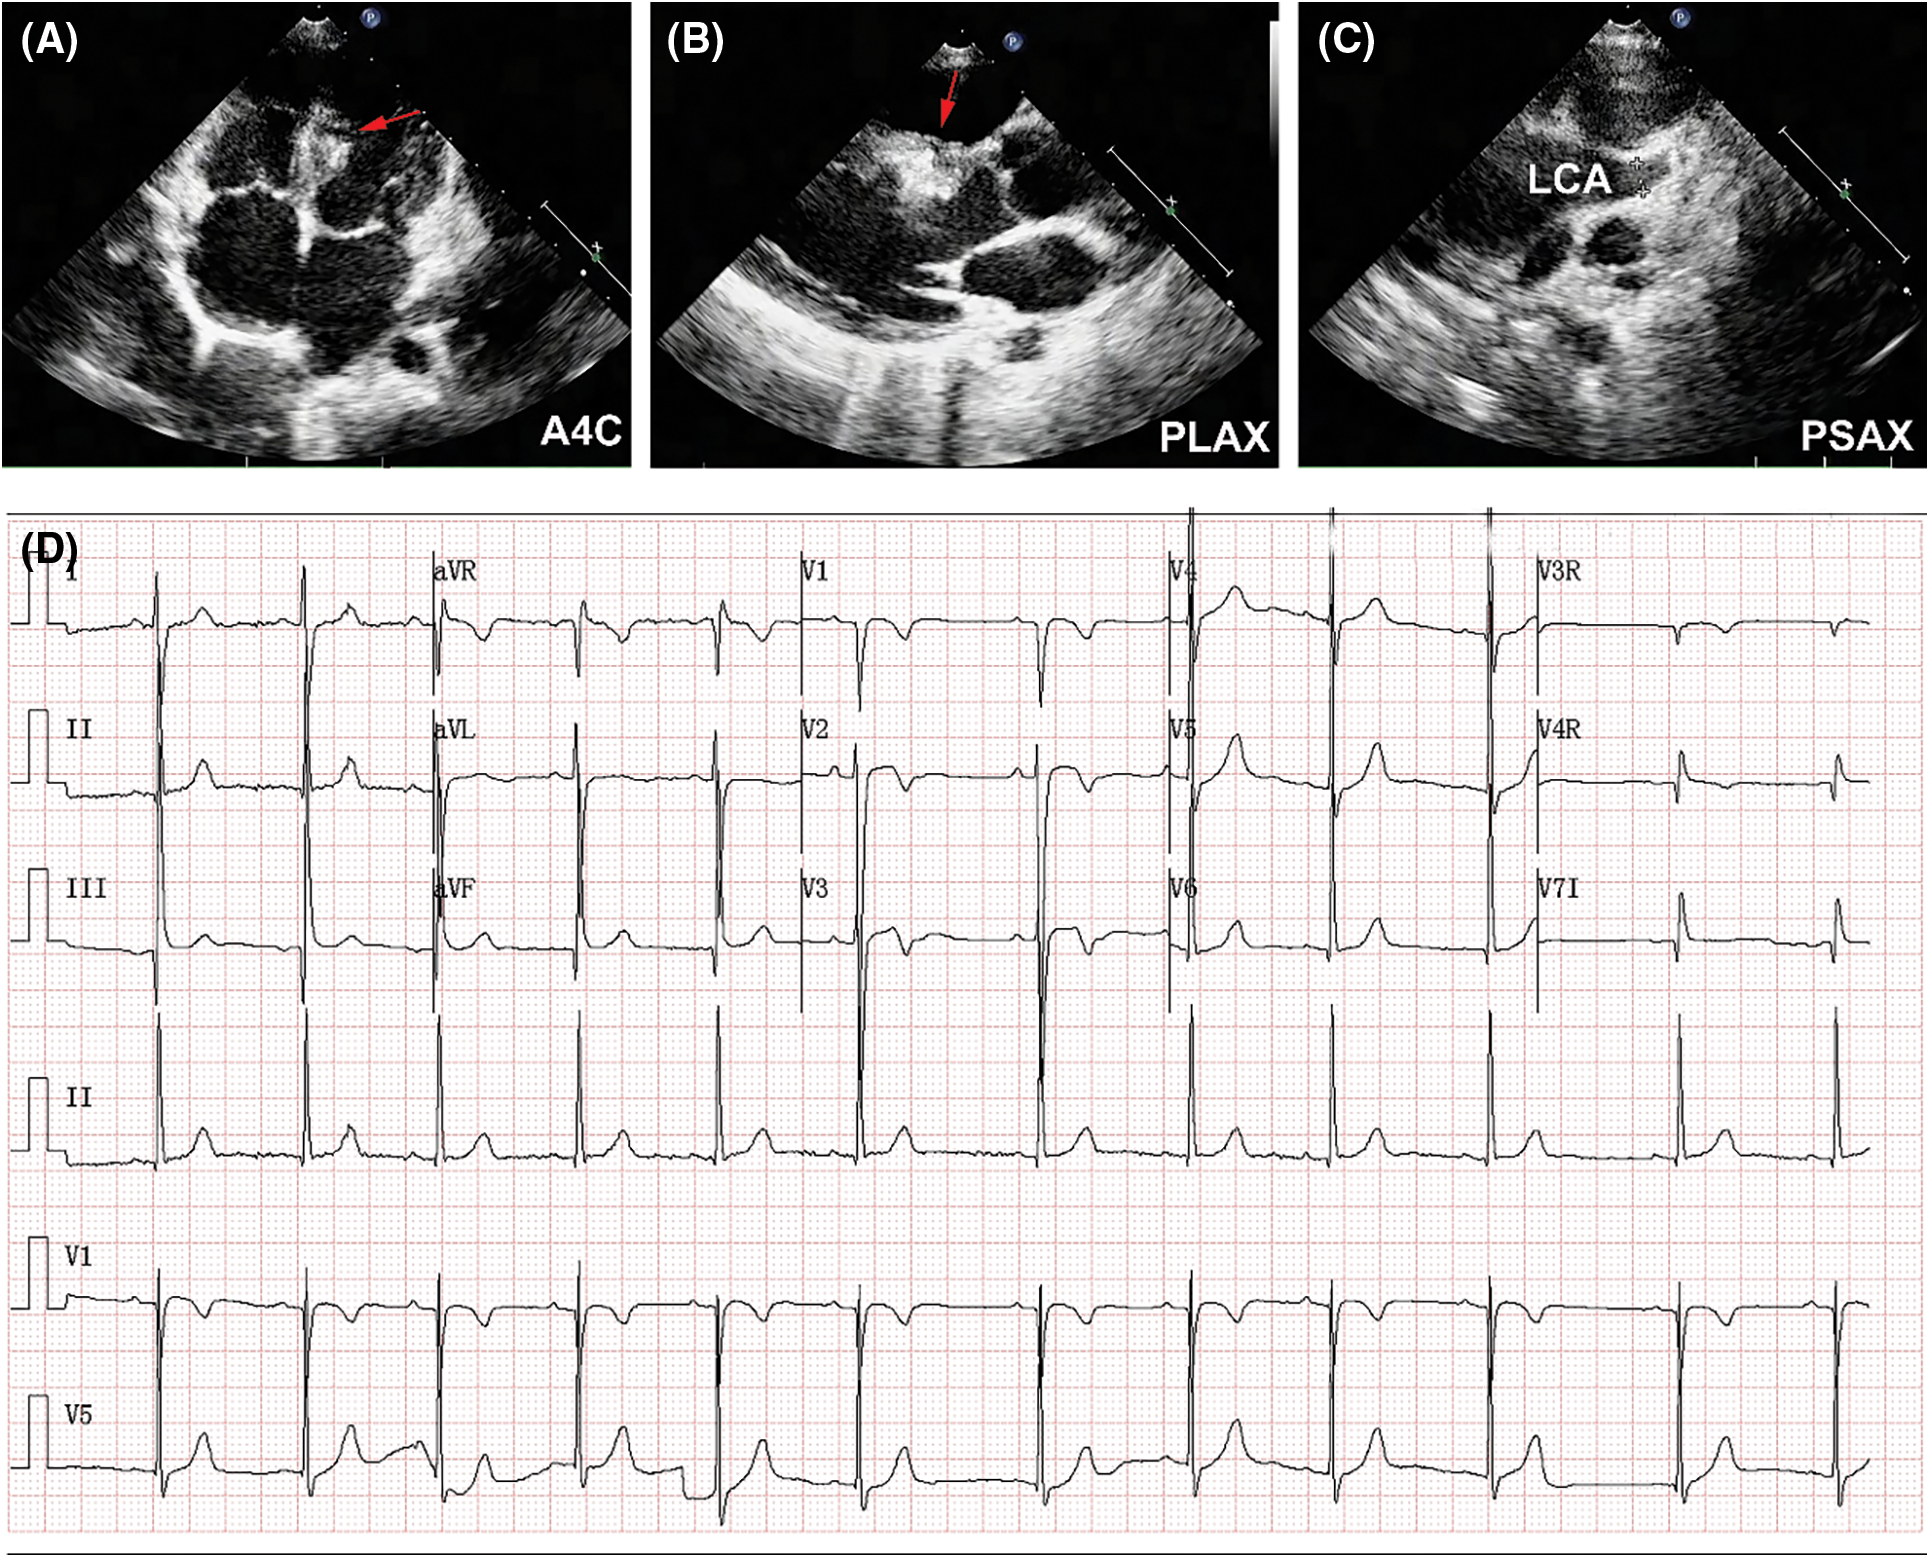

At postoperative day 1, the patient experienced elevation of cardiac troponin T (TnT, peak of 448 pg/mL; normal values < 14 pg/mL) and creatine kinase-MB (CK-MB, peak of 41.9 U/L; normal values < 24 U/L). Although no elevation of ST segment or ST-T changes was detected in ECG, her 24-h holter monitoring showed period of junctional escape rhythm and aberrant ventricular conduction, indicating potential myocardial ischemia (Figs. 4A and 4B). TTE demonstrated both devices were well located, without apparent residual shunt (Figs. 5A and 5B). Thrombus formation was detected within the CAA (Fig. 5C), and LCA ostium was still dilated (Fig. 5D). The patient was given dual antiplatelet therapy with aspirin (5 mg/kg) and clopidogrel (1 mg/kg). The remaining postoperative course was uneventful. Her ECG returned to normal sinus rhythm at postoperative day 2, and level of CK-MB returned to normal level (21 U/L). The patient recovered well and was discharged at postoperative day 7 post procedure without complications.

Figure 4: ECG results at postoperative day 1. (A) ECG showed sinus tachycardia. (B) 24-h holter monitoring showed period of junctional escape rhythm and aberrant ventricular conduction

Figure 5: TTE results at postoperative day 1. (A) The AVP II (red arrow) was located at the inlet of fistula without residual shunt in parasternal long-axis view (PLAX). (B)The ADO II (red arrow) was located at the outlet of fistula without residual shunt (A4C). (C) Thrombus formation (red arrow) was detected within the CAA (A4C). (D) LCA was still significantly dilated (PSAX)